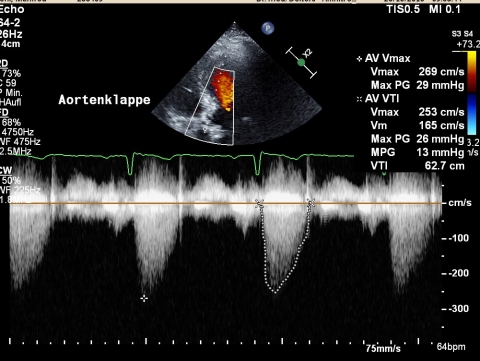

Ultraschall_Herz_Aortenklappe_Praxis_Dr_Deiters